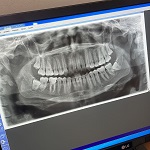

El primero de estos operativos se realizó el sábado 11 de mayo, y el segundo el sábado 18. En total, 56 pacientes en lista de espera desde 2021 a 2023 fueron atendidos en el área odontológica. A cada uno se le tomó una radiografía panorámica, y en ambos fines de semana se realizaron también dos tomografías computarizadas Cone Beam (de haz cónico), técnica de alta resolución que permite visualizar en tres dimensiones las estructuras dentales, óseas faciales y craneales. Esta información es clave para la planificación quirúrgica.